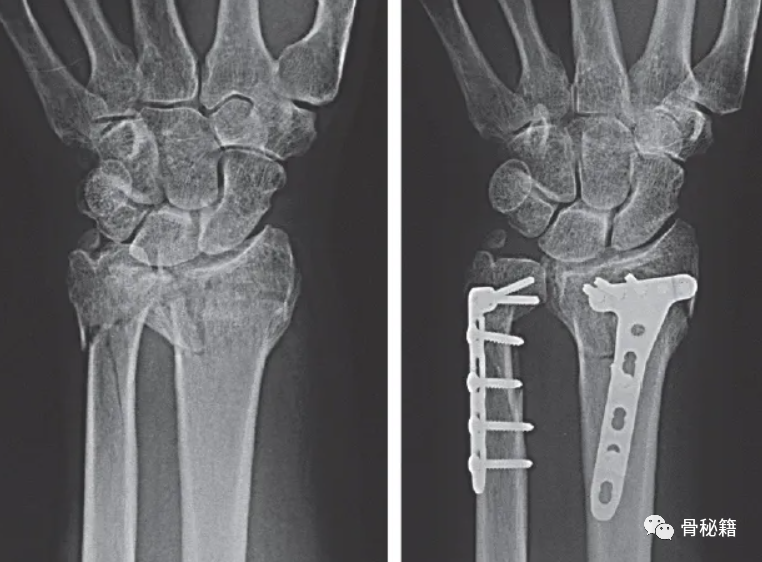

尺骨茎突基部骨折使 DRUJ 的稳定性受到质疑

采用茎突入路进行手术复位与固定,拧入空心螺钉

固定后 术中用探钩检查TFCC稳定性,发现固定后稳定性较好